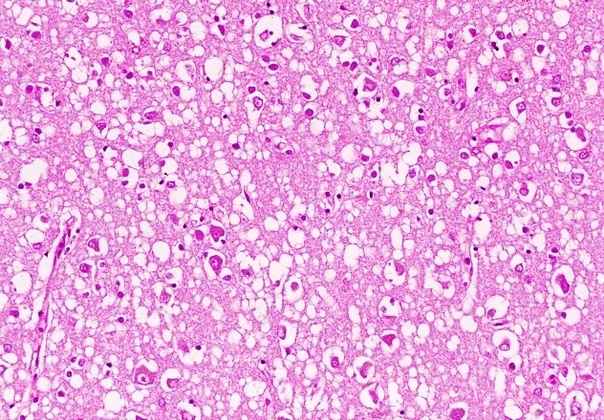

При болезни куру патологические изменения можно наблюдать только в центральной нервной системе. Обычно они выражаются в формировании типичной губчатой энцефалопатии. В коре, подкорковых ядрах, подбугорной области и в мозжечке наблюдается вакуолизация дендритов, аксонов и тел нейронов. Вакуолизация становится настолько выраженной, что серое вещество коры большого мозга приобретает вид губки, в результате чего такое состояние обозначают как status spongiosus. Методом электронной микроскопии было выяснено, что вакуоли окружены фрагментами таких же пролиферирующих мембран. Характерный патогистологический признак при куру – выпадение нейронов.

головного мозга

страдавшего от болезни

взрослого мужчины,

который впоследствии

погиб от куру

Изменения нейронов сочетаются с гипертрофией и размножением астроцитов. При куру у человека патогистологические изменения наиболее выражены в мозжечке: появляются аморфные ШИК-положительные бляшки, содержащие амилоид, уменьшается количество грушевидных нейронов (клеток Пуркинье). Вместе с тем, при куру не удаётся обнаружить воспалительной реакции, столь характерной для многих заболеваний ЦНС, или таких характерных признаков вирусной инфекции, как образование телец включений или глиальных узлов.

Характерные для куру изменения ЦНС обнаруживаются ещё до появления клинических симптомов заболевания, что сопровождается снижением общего содержания ганглиозидов в сером веществе головного мозга на 40%. Однако сам прион не удаётся обнаружить ни в крови, ни в сыворотке, ни в моче, ни в спинномозговой жидкости. В молоке, ткани плаценты и амниотической жидкости у людей или экспериментально заражённых животных прион также не обнаруживается.

Таким образом, морфологически прионные болезни можно отнести к группе амилоидозов. Амилоидоз при прионных болезнях характеризуется отложением волокнистого амилоидного белка в головном мозгу. Образование прионных амилоидных бляшек сближает прионнные болезни с амилоидозами из группы нейродегенеративных заболеваний, таких, как, например, хорея Гентингтона. Получены убедительные доказательства того, что свойства прионных белков и амилоидов идентичны.

Тем не менее, при большом сходстве патогистологических изменений между болезнями Крейтцфельдта-Якоба, куру и скрепи имеются отличия. Так, амилоидные бляшки при болезни Кройцфельдта-Якоба наблюдаются в 9%, а при куру они встречаются в 70% случаев.

Уже давно было подмечено, что все симптомы при болезни Кройтцфельдта-Якоба подкрепляются патогистологическими изменениями. Так, при изменении моторных нейронов отмечено выпадение многих нервных клеток в двигательной области коры, включая гигантские пирамидные нейроны (клетки Беца), а также демиелинизацию пирамидных путей и утрату клеток передних рогов спинного мозга.

болезни Кройтцфельда-Якоба